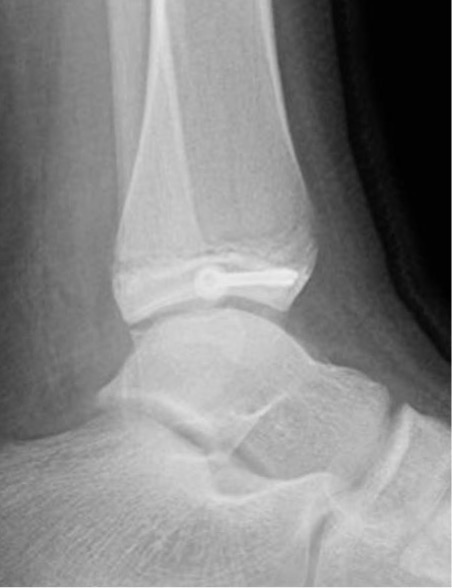

| SH III distal tibia / Tillaux | Triplanar fracture |

| Low risk growth arrest / physeal bar | 1% growth arrest as adolescent patients |